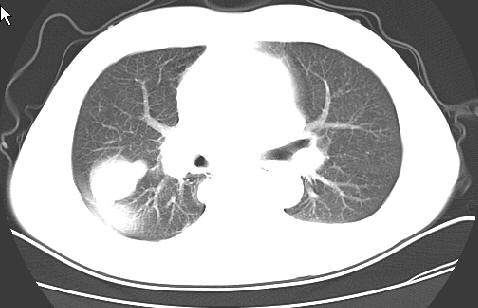

以下是引用草之原在2009-5-2 19:29:00的发言:[br]1.考虑右侧中心型肺ca纵膈淋巴结转移,双侧胸腔积液及右侧叶间裂积液,心包积液。[br]2.两肺上叶病灶,纵膈窗显示部分病灶硬化,考虑:结核。[br][br] [br]

以下是引用ct诊断高手在2009-5-2 19:08:00的发言:[br]我考虑右侧中央型肺癌 伴右肺节段性不张,两肺及纵隔淋巴结转移,右侧胸腔积液。

以下是引用zjzjr在2009-5-2 20:16:00的发言:[br]肺结核,转移瘤.纵隔淋巴结转移或淋巴瘤,右侧包裹性积液、斜裂积液。心包积液。